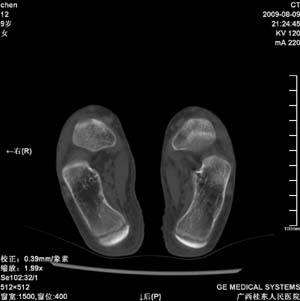

标题: PED2867:右侧内踝肿胀,骨质改变,请各位老师会诊 [打印本页]

标题: PED2867:右侧内踝肿胀,骨质改变,请各位老师会诊

九岁小朋友,近期左侧内踝疼痛,局部肿胀,平时无特殊,近期经常溜干冰

对不起,是右侧内踝肿胀

双侧踝关节骨质及关节结构均未见明显异常。考虑玩多了累的,休息休息看看吧!

骨质及关节结构未见异常。